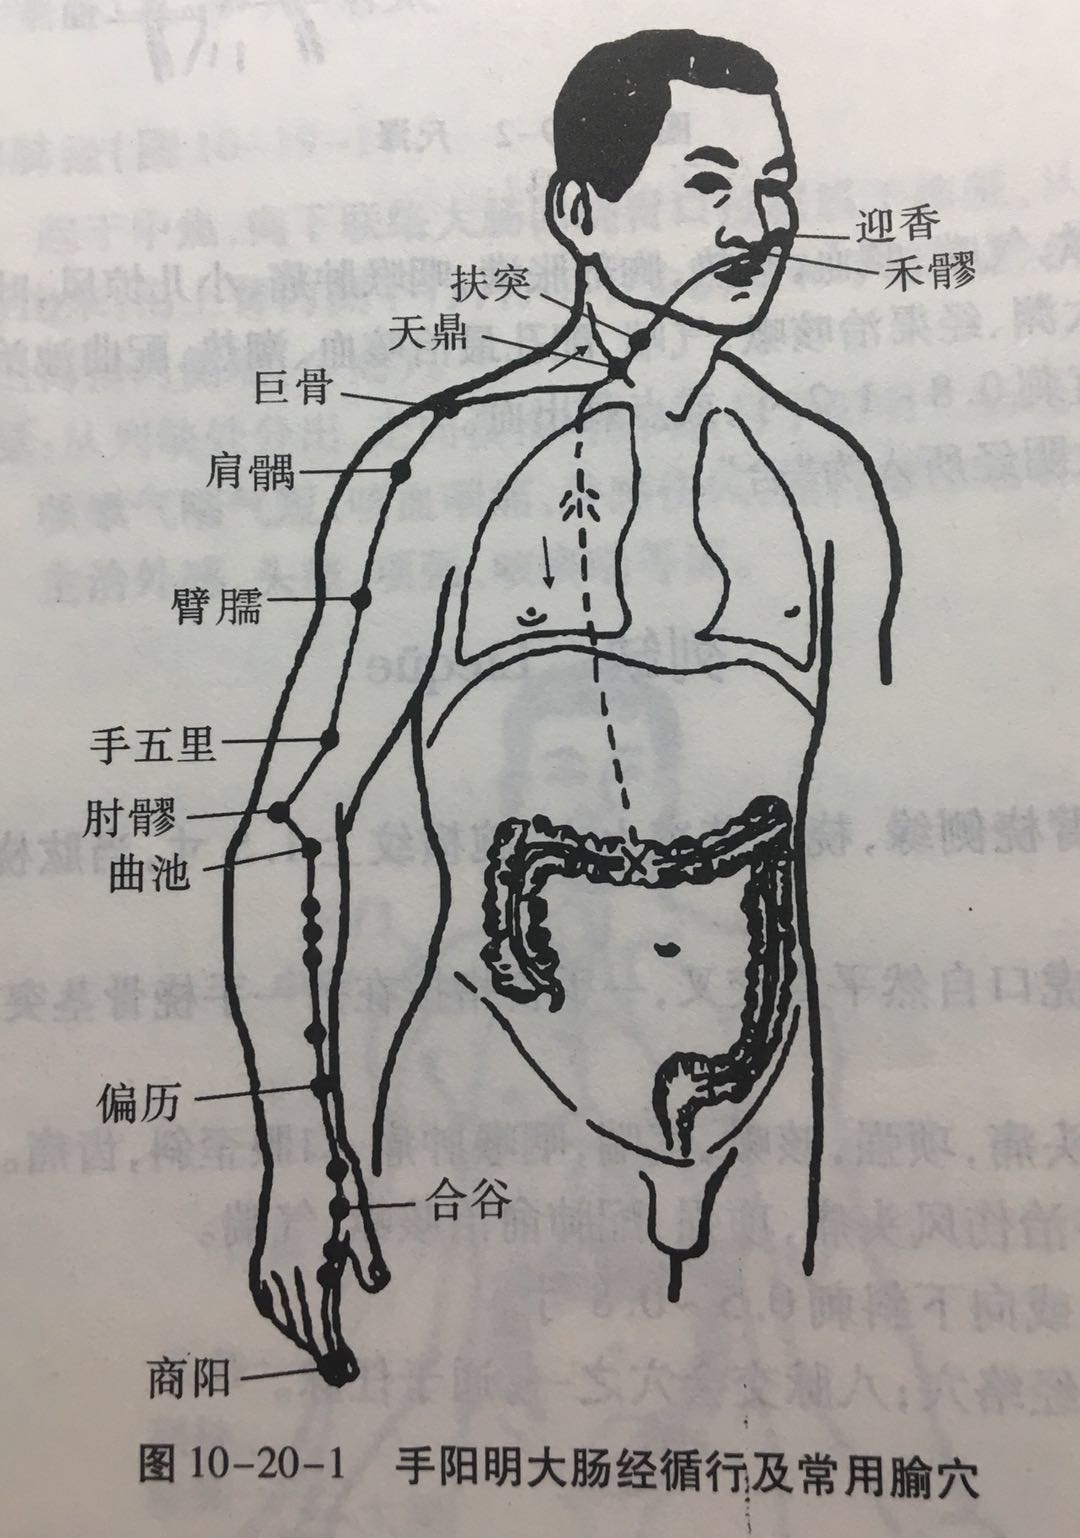

【(二)手阳明大肠经(图10-20-1)】

1、时辰 卯(mǎo)时 5 ~ 7

2、歌诀 手阳明穴起商阳,二间三间合谷藏,阳溪偏历历温溜,下廉上廉三里长,曲池肘髎(liáo)迎五里,臂臑(nào)肩髎(liáo)巨骨起,天鼎浮突接禾髎(liáo),终以迎香二十止。

3、经脉循行 起于食指末端(商阳),沿食指外(桡)侧向上,通过一、二掌骨之间(合谷)向上进入两筋(拇长伸肌腱与拇短伸肌腱)之间的凹陷处,沿前臂前方,至肘部外侧,再沿上臂外侧前缘,上走肩端(肩髃(yú)),沿肩峰前缘向上出于颈椎(大椎),再向下入缺盆(锁骨上窝)部,联络肺脏,通过横膈,属于大肠。

缺盆部支脉:上走颈部,通过面颊,进入下齿龈,回绕止上唇,交叉于人中,左脉向右,右脉向左,分布在鼻孔两侧(迎香),与足阳明胃经相接。

从食指末端起始(商阳),沿食指桡侧缘(二间、三间),出第一、二掌骨间(合谷)、进入两筋(拇长伸肌腱和拇短伸肌腱)之间(阳溪),沿前臂桡侧(偏历、温溜、下廉、上廉、手三里),进入肘外侧(曲池、肘髎),经上臂外侧前边(手五里、臂臑),上肩,出肩峰部前边(肩髃、巨骨,会秉风),向上交会颈部(会大椎),下入缺盆(锁骨上窝),络于肺,通过横膈,属于大肠。

它的支脉:从锁骨上窝上行颈旁(天鼎、扶突),通过面颊,进入下齿槽,出来挟口旁(会地仓),交会人中部(会水沟)--左边的向右,右边的向左,上夹鼻孔旁(锁骨上窝),络于肺,通过横膈,属于大肠。

4、主要证候 腹痛、肠鸣、泄泻、便秘、咽喉肿痛、齿痛。本经循行部位疼痛、热肿或寒冷麻木等。

5、主治概要 主治头面、五官、咽喉病、热病及经脉循行部位的其他病证。